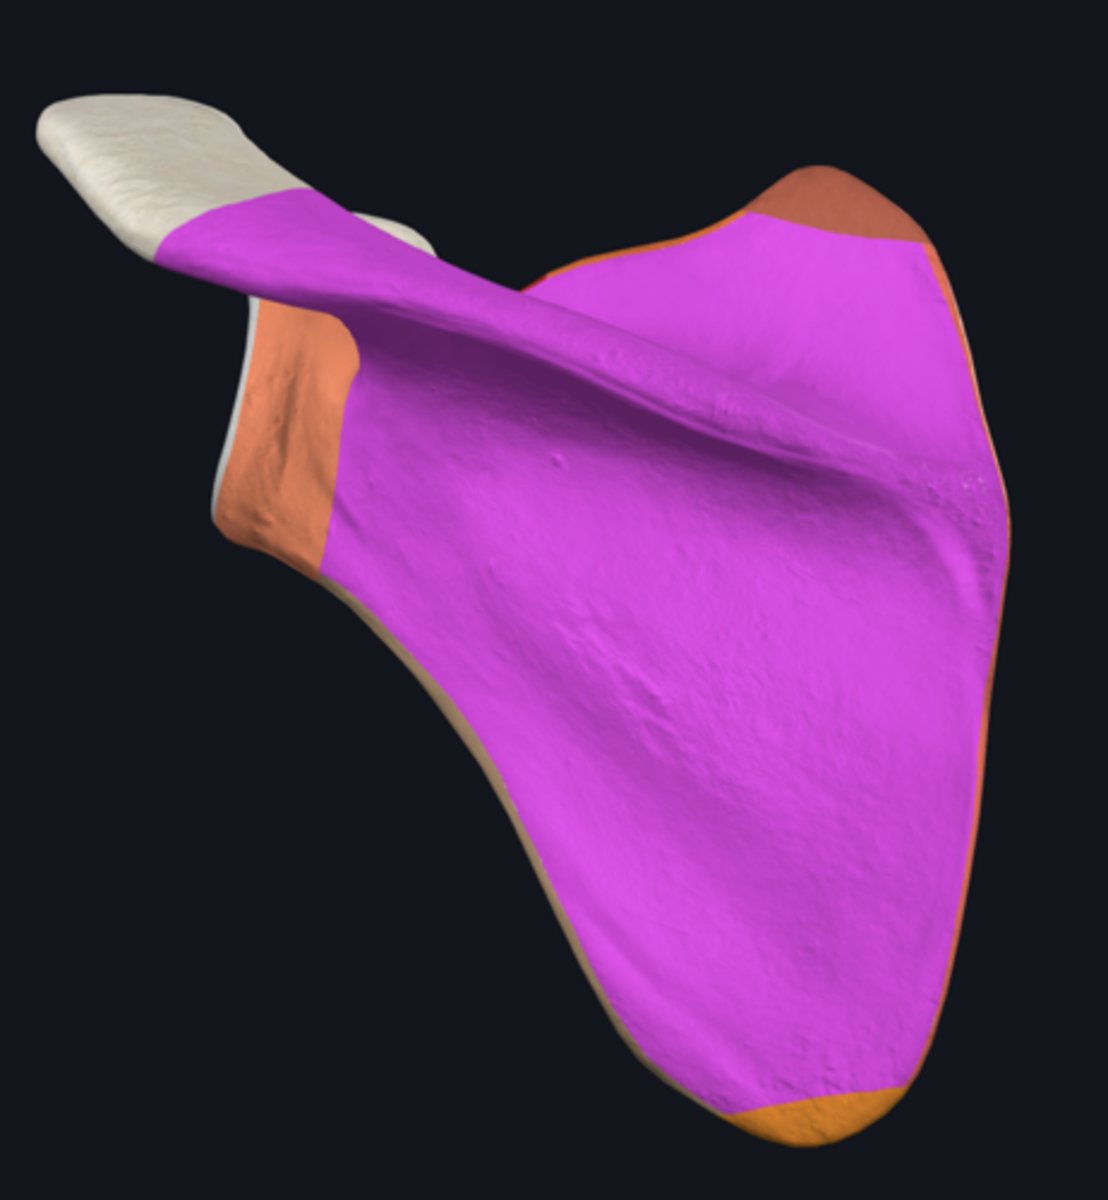

Acromion

Coracoid process

posterior surface of scapula

superior border of scapula

infraspinous fossa

spine of scapula

subscapular fossa

supraspinous fossa